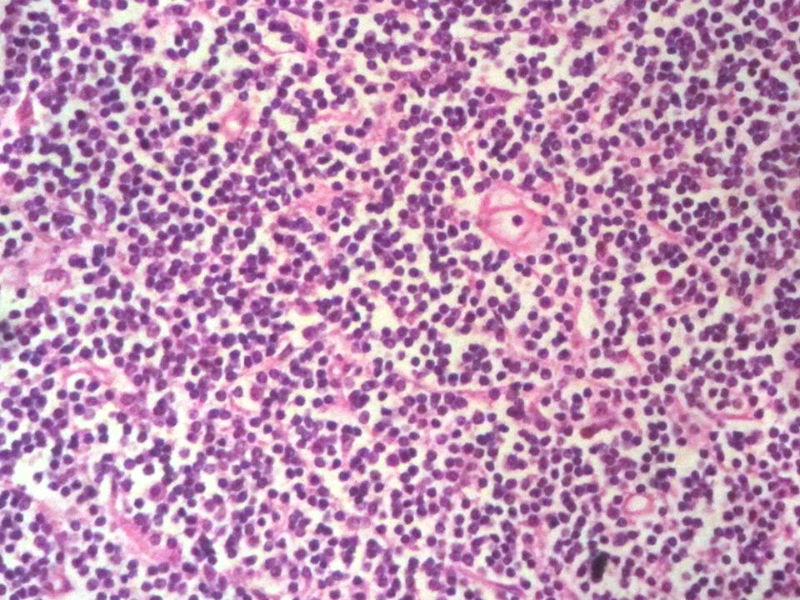

男,49岁,左眼睑球结膜下肿物2个月,手术切除。检查肿块3X2X2厘米,切面灰红色,质软。

本例是发生在特殊部位“结膜下”,HE肿瘤细胞形态形态一致,形似单核样B细胞。B细胞标记若明确阳性,诊断MALT是挺合理的。

HE:  1.MALT粘膜相关淋巴瘤:本例部位很特殊,位于“结膜下”,考虑MALT很合理;但本例镜下细胞形态很一致,诊断MALT是有难度的。

2. SLL小细胞淋巴瘤:就细胞形态而言,有相似之处,考虑SLL也有道理;但如果在没有发现淋巴结,肝,脾,骨髓或外周血具有病变的前题下,原发于结膜的SLL可能是少见的。

3.套细胞淋巴瘤:细胞大小及一致性比较符合;但本例核太规则了,套细胞淋巴瘤很难有这么规则的圆形或椭圆形。

4.滤泡性淋巴瘤: 可能性更小,暂时不考虑。

淋巴样细胞。细胞形态单一,细胞小。主要鉴别:

1)粘膜相关淋巴组织淋巴瘤

2)小细胞性淋巴瘤/慢性淋巴细胞性白血病

3)套细胞淋巴瘤

形态结构与细胞大小,似不支持滤泡性淋巴瘤。

淋巴瘤  细胞小  形态单一  主要考虑小B细胞淋巴瘤